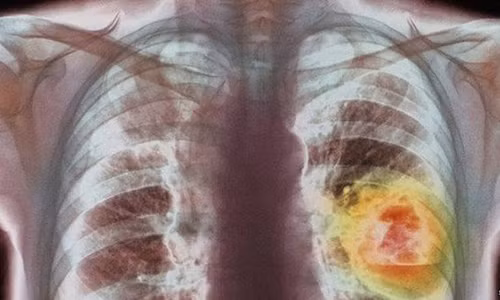

Theo các nhà khoa học, ung thư phổi còn được gọi là ung thư phế quản là bệnh lý ác tính, phát triển từ biểu mô phế quản, tiểu phế quản, phế nang hoặc từ các tuyến của phế quản.

Bệnh diễn biến âm thầm và gây tử vong cao. Giống như các bệnh ung thư, ung thư phổi bắt đầu khi một hoặc nhiều tế bào phân chia một cách mất kiểm soát. Sau nhiều lần như vậy hình thành một khối tế bào nhỏ đường kính khoảng 1cm.

Nếu các tế bào này tiếp tục nhân lên thì khối này tiếp tục gia tăng về kích thước. Ở một số giai đoạn, những tế bào có thể rời khỏi khối u ban đầu và lưu hành đến các phần khác của cơ thể và phát triển thành khối u mới.

| Ung thư phổi gây tổn hại sức khỏe con người vô cùng nhanh chóng. (Ảnh minh họa: Afamily) |

Những khối u ở phổi có thể gây chảy máu, làm tắc nghẽn đường hô hấp, gây ho, khó thở hay nhiễm khuẩn. Khối u có thể phát triển ra thành ngực gây đau. Đôi khi ung thư phổi có thể phát triển to và bệnh nhân không có triệu chứng.

Đặc điểm diễn biến về mặt sinh học của ung thư phổi là lan rộng và di căn. Do vậy, 90% bệnh nhân mắc bệnh ung thư phổi sẽ tử vong trong vòng 1 - 2 năm.